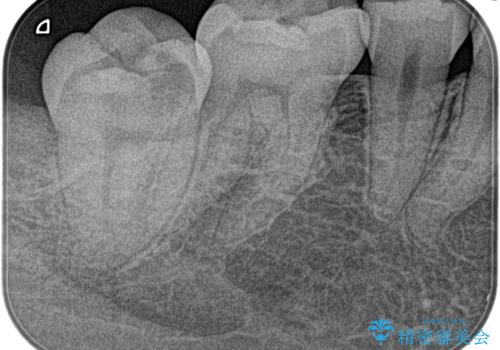

- 3日前からズキズキ痛み、冷たいものや熱いもので持続痛もあるとのこと。

不可逆性歯髄炎の診断で抜髄処置を行なっています。